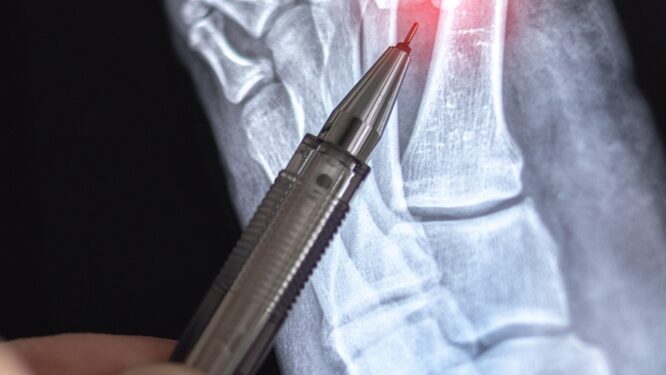

Nustatant Lisfranco sužalojimą, atliekamas fizinis pėdos ištyrimas, atsižvelgiama į jos išvaizdą, jautrumą ir stabilumą. Taip pat svarbu tiksliai apibūdinti, kaip susižalojote ar kada pirmąkart pajutote simptomus.

Norint patikslinti diagnozę, gali būti atliekami instrumentiniai tyrimai:

- Pėdos rentgeno nuotrauka;

- Magnetinio rezonanso tomografija (MRT);

- Kompiuterinė tomografija (KT).

Šie tyrimai leidžia įvertinti, ar pažeisti kaulai, raiščiai, ar abu.